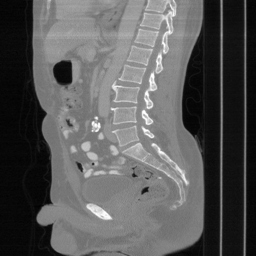

| Ground Truth | Input | DDS-100 [chungdecomposed] | DDS-200 [chungdecomposed] | NERD-P (Ours) |

![]() |

| PSNR = dB | PSNR = 14.56 dB | PSNR = 37.42 dB | PSNR = 37.81 dB | PSNR = 39.15 dB |

Main results: In Table 1, we present quantitative results and in Figure 2, we show visualizations in the axial, coronal, and sagittal planes. Our methods consistently outperform the second-best baseline across most views, achieving nearly 1 dB higher PSNR on average. Despite incorporating a few additional input updates to enforce data consistency, our method reaches competitive performance with only 30 sampling steps. Based on the visualizations, we observe that DDS introduces slight artifacts along the horizontal direction, particularly noticeable in the coronal and sagittal views. In contrast, our method produces cleaner reconstructions with fewer artifacts in these orientations.